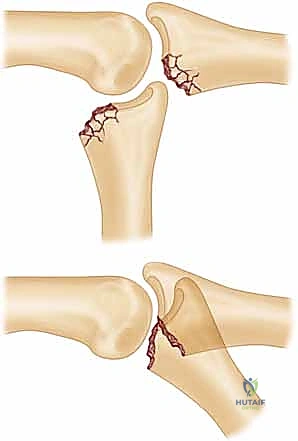

* FIG 1 • A. Unstable PIP fracture-dislocation. The upward pull of the central tendon insertion and the distal superficialis insertion pull and push the middle phalanx up and over the proximal phalangeal head. The only forces preventing dorsal subluxation are the middle phalanx palmar lip and the palmar plate, both of which are lost in an unstable PIP palmar lip fracture.

* FIG 1 • B. PIP instability after a fracture. A direct relation exists between the amount of middle phalanx palmar lip destroyed by the fracture and the resultant PIP joint stability. Articular damage in excess of 50% of the joint surface always renders the joint unstable, whereas fractures involving less than 30% usually are stable. Tenuous fractures (ie, those with articular damage of 30% to 50% of the joint surface), must be assessed with lateral radiographs. If the joint will not stay reduced with less than 30 degrees of flexion, it must be classified as “unstable.”